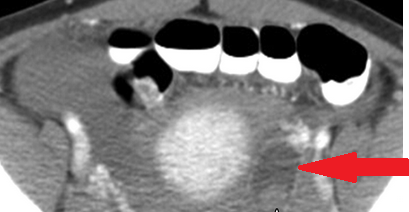

Αυτόματη ρήξη/αιμορραγία νεφρού — αγγειομυολίπωμα (Ευγενική παραχώρηση Dr. V. Penopoulos)